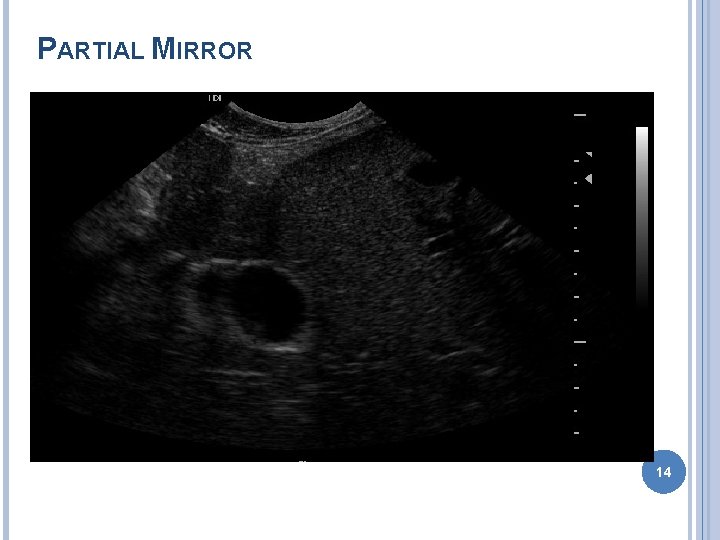

ARTIFACTS Improper machine settings – gain Reverberation � Mirror image – liver GB � Comet tail – gas bubble � Ring down – skin transducer surface Acoustic shadowing Acoustic enhancement Edge enhancement � Border of kidney 11

PARTIAL MIRROR 14